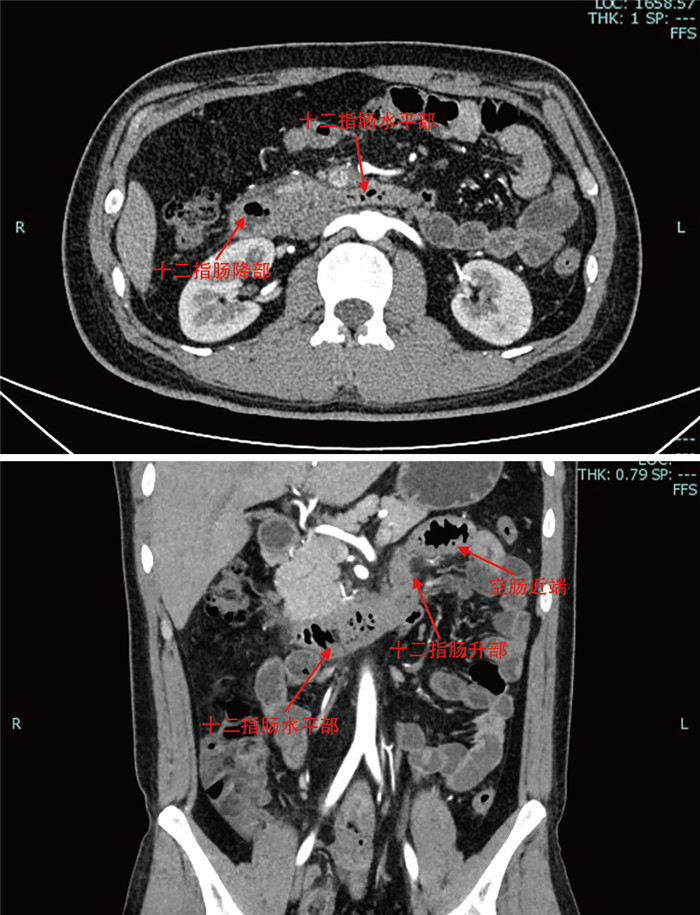

成人腹型过敏性紫癜误诊1例并文献复习

罗利绵, 李琪, 谢淼

2025, 23(7): 1262-1266. doi: 10.16766/j.cnki.issn.1674-4152.004111

443 8

摘要:

通过回顾成人腹型过敏性紫癜误诊病例,分析原因并结合临床文献资料,总结腹型过敏性紫癜疾病特点,降低误诊率。本文回顾分析了2022年7月收治的1例被误诊为急性胃肠炎的成人腹型过敏性紫癜患者的临床资料,该例患者在腹痛后期出现皮肤紫癜,同时寻求多学科会诊,更改诊断为腹型过敏性紫癜,予以糖皮质激素、抗过敏药物等对症治疗后病情好转出院。腹型过敏性紫癜少见,而成人发病率更低,因缺乏特征性临床表现及特异性辅助检查,误诊率高,临床工作者应吸取经验教训,避免误诊错治。